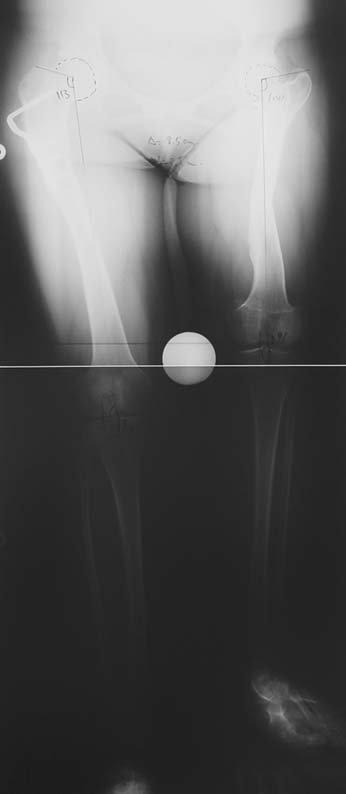

Bu işlemin ne zaman ve hangi kemik segmentlerine uygulanacağı değişik metodlarla (Gren-Anderson şeması; Moseley eğrisi; Paley’in multiplier metodu gibi.) tedaviyi yapacak doktor tarafından hesaplanmalıdır. Yetişkinlerde büyüme çekirdekleri kapanmış olduğu için epifizyodez bir seçenek değildir. Yetişkinde uzun bir bacağı kısaltmak için kemikten bir parça cerrahi olarak çıkartılmalıdır. Bu genellikle femurda (uyluk kemiği) yapılır ve kemik intramedüller çivi ile tespit edilir. Bu yöntemin en büyük avantajı 5cm´den az uzunluk farklarında boy eşitliğini hemen sağlamasıdır. Hem epifizyodezin hem de kısaltmanın ortak dezavantajı hastanın toplam boyunun kısalmasıdır. 5cm’ den fazla kısaltma tavsiye etmediğimiz için boy kaybı hiçbir zaman 5 cm’ den fazla olmamaktadır. 5cm’den daha az boy farklılıkları için kısaltma veya epifizyodez ameliyatı olmak istemeyen hastalarda bacak boyunu eşitlemek için bacak uzatma işlemi tercih edilmelidir. İkinci bir uzatma ihtiyacını azaltmak veya uzatma miktarını azaltmak için epifizyodez ve kısaltma uzatma ile kombine ederek uygulanabilir.